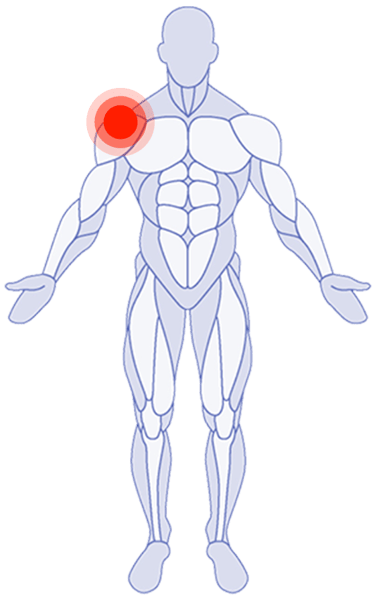

Where Do You Need Attention?

Use the latest research in physical therapy to work better, play better and spend more time on what really matters.

Shoulder Pain